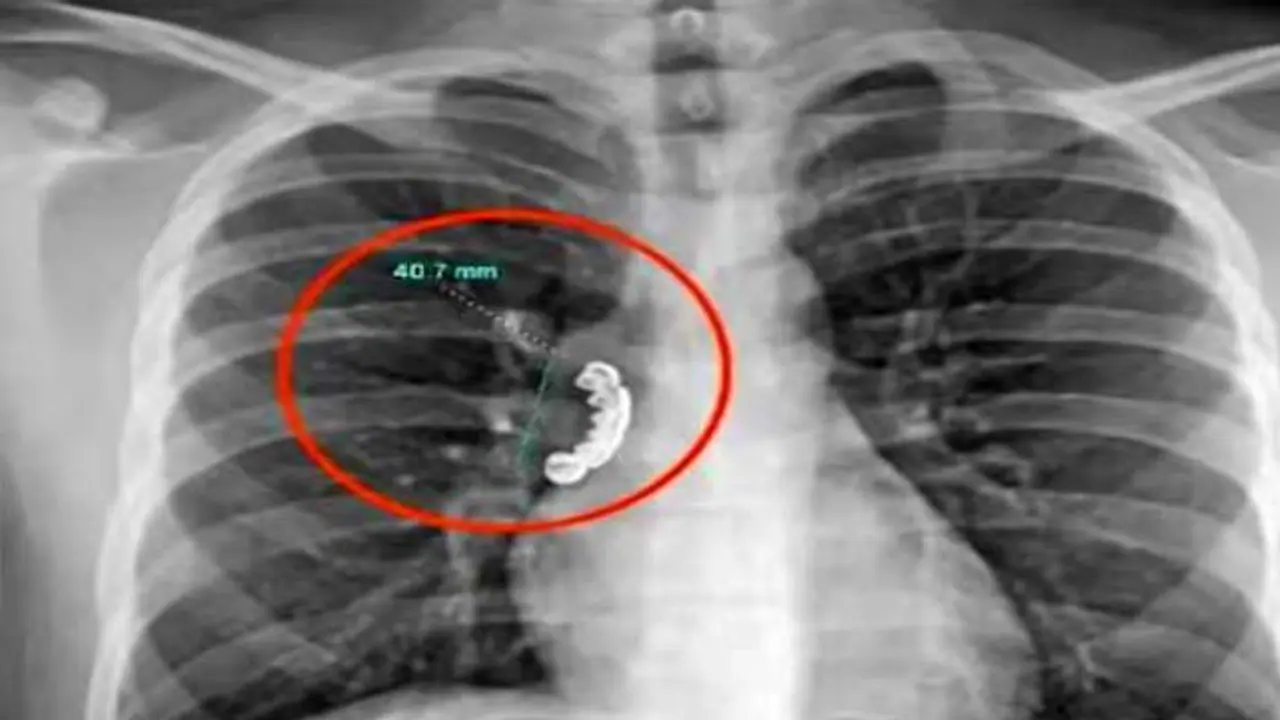

वह एक दिन अजीब दुर्घटना का शिकार हो गया। दरअसल, वह एक दिन खाना खा रहा था तभी दांतों में लगा डेन्चर निकलकर उसके गले में फंस गया। 1.5 इंच का यह नकली दांत इतना अंदर तक चला गया कि उसे सांस लेने में दिक्कत होने लगी और उसका दम घुटने लगा।

आन-फानन में युवक को अस्पताल ले जाया गया। जहां डॉक्टरों ने उसका एक्सरे किया। डॉक्टर उसका एक्सरे देख कर दंग रह गए।उसके गले में काफी अंदर जाकर डेन्चर फंसा गया था। इसके बाद डॉक्टरों ने एक लचीली ट्यूब डालकर उसे निकालने की कोशिश हुई तो वह और भी अंदर चला गया। बाद में ऑपरेशन करके डेन्चर को बाहर निकाला गया। तब जाकर इस शख्स की जान बच पाई।

डॉक्टरों ने बताया कि अगर उसे अस्पताल लाने में कुछ और देर हो जाती तो उसकी दम घुटने की वजह से मौत तक हो सकती थी।क्योंकि डेन्चर फंसने की वजह से उसकी सांस बिल्कुल भी अंदर बाहर नहीं हो रही थी। फेफड़े के वायुमार्ग की मांसपेशियां टाइट हो गई थीं।